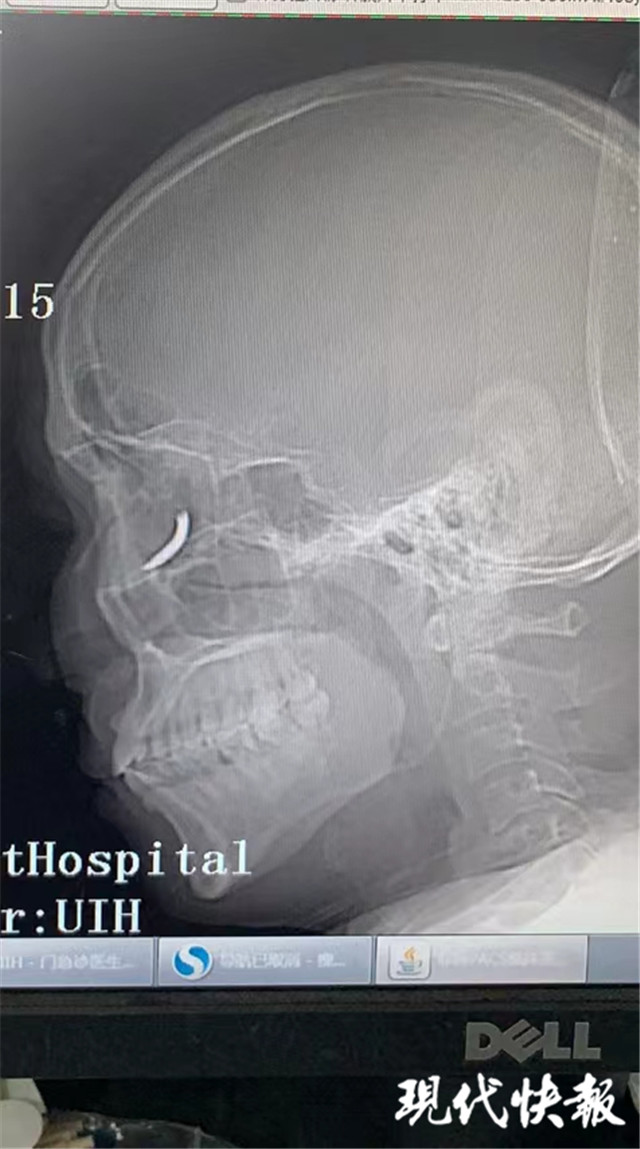

(通訊員 孫忠河 記者 梅書華)鐵釘扎入眼眶,卻不疼不癢,這是怎么回事?三天前,王師傅在溧水的建筑工地干活時(shí),突然感覺有異物進(jìn)入眼內(nèi),但沒當(dāng)回事,后來出現(xiàn)頭暈才就診,沒想到是鐵釘扎入了眼眶。南京市第一醫(yī)院醫(yī)生通過半小時(shí)手術(shù),順利將一根長約一公分的鐵釘取出。

“當(dāng)時(shí)在敲鐵釘,感覺什么東西進(jìn)眼睛里了,但沒影響視力,還以為是水泥灰之類的。”三天前,王師傅眼中進(jìn)入異物,感覺頭暈不適后,去當(dāng)?shù)蒯t(yī)院就診,拍了X光片后,竟然發(fā)現(xiàn)自己眼眶內(nèi)有一個鐵釘樣的異物。

隨即,王師傅趕到南京市第一醫(yī)院眼科就診,眼科門診曹雪倩醫(yī)生接診后,立即完善CT等相關(guān)檢查。剛準(zhǔn)備休息的眼科醫(yī)生范偉杰,立即與副主任醫(yī)師趙貴陽聯(lián)合研究這個特殊的病例。專家們發(fā)現(xiàn)這枚鐵釘不偏不倚正好扎進(jìn)病人的眼眶里,但是眼眶內(nèi)解剖結(jié)構(gòu)復(fù)雜,要在盡可能保護(hù)正常組織結(jié)構(gòu)的情況下完成探查并取除鐵釘,手術(shù)難度較大。

范偉杰與趙貴陽反復(fù)討論后,制定了詳細(xì)周密的手術(shù)方案,最終以局麻下、眼袋美容切口進(jìn)入,順利取出了一根長約一公分的鐵釘。整臺手術(shù)耗時(shí)半小時(shí),手術(shù)過程中沒有損傷到眼球壁和視神經(jīng),但醫(yī)生發(fā)現(xiàn)因?yàn)殍F釘?shù)那秩?,視網(wǎng)膜周邊有出血,所以做了視網(wǎng)膜光凝。術(shù)后視力1.0,面部看不出瘢痕。王師傅的眼球終于安全保住了。